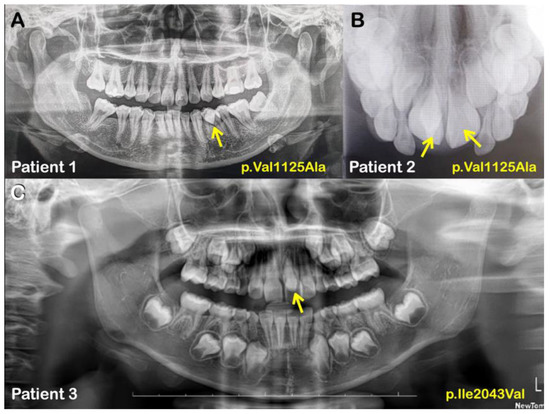

| Families | Patients | Phenotypes | APC Variants NM_000038.6; NP_000029.2 | Prediction/Ranking |

|---|---|---|---|---|

| 4 | Normal mother | No variants | MutationTaster: Disease causing Prob = 0.999223891277048 Polyphen-2: Probably damaging; score = 0.936 SIFT: Tolerated; score = 0.068 CADD-PHRED score = 22.2 DANN score = 0.9909 | |

| 4 (Male) | Mesiodens (Double; unerupted & inverted) | c.8383G>A p.Ala2795Thr chr5-112179674-G-A rs369264968 MAF:0.00004400 | ||

| 5 (Male) | Mesiodens (Double; both were erupted) | |||

| Normal sister | No variants | |||

| 5 | 6 (Male) | Mesiodens (Double; unerupted) One is inverted, the other had normal orientation | Variant 1 c.2740T>G p.Cys914Gly chr5-112174031-T-G rs1554084426 Not reported in gnomAD Variant 2 c.5722A>T p.Asn1908Tyr chr5-112177013-A-T No rs number Not reported in gnomAD | Variant 1 MutationTaster: Disease causing Prob = 0.99929839701033 Polyphen-2: Benign score = 0.055 SIFT: Tolerated; score = 0.127 CADD-PHRED score = 21.5 DANN score = 0.8956 Variant 2 MutationTaster: Polymorphism Prob = 0.999999988244843 Polyphen-2: Benign score = 0.214 SIFT: Damaging; score = 0.046 CADD-PHRED score = 17.19 DANN score = 0.9609 |